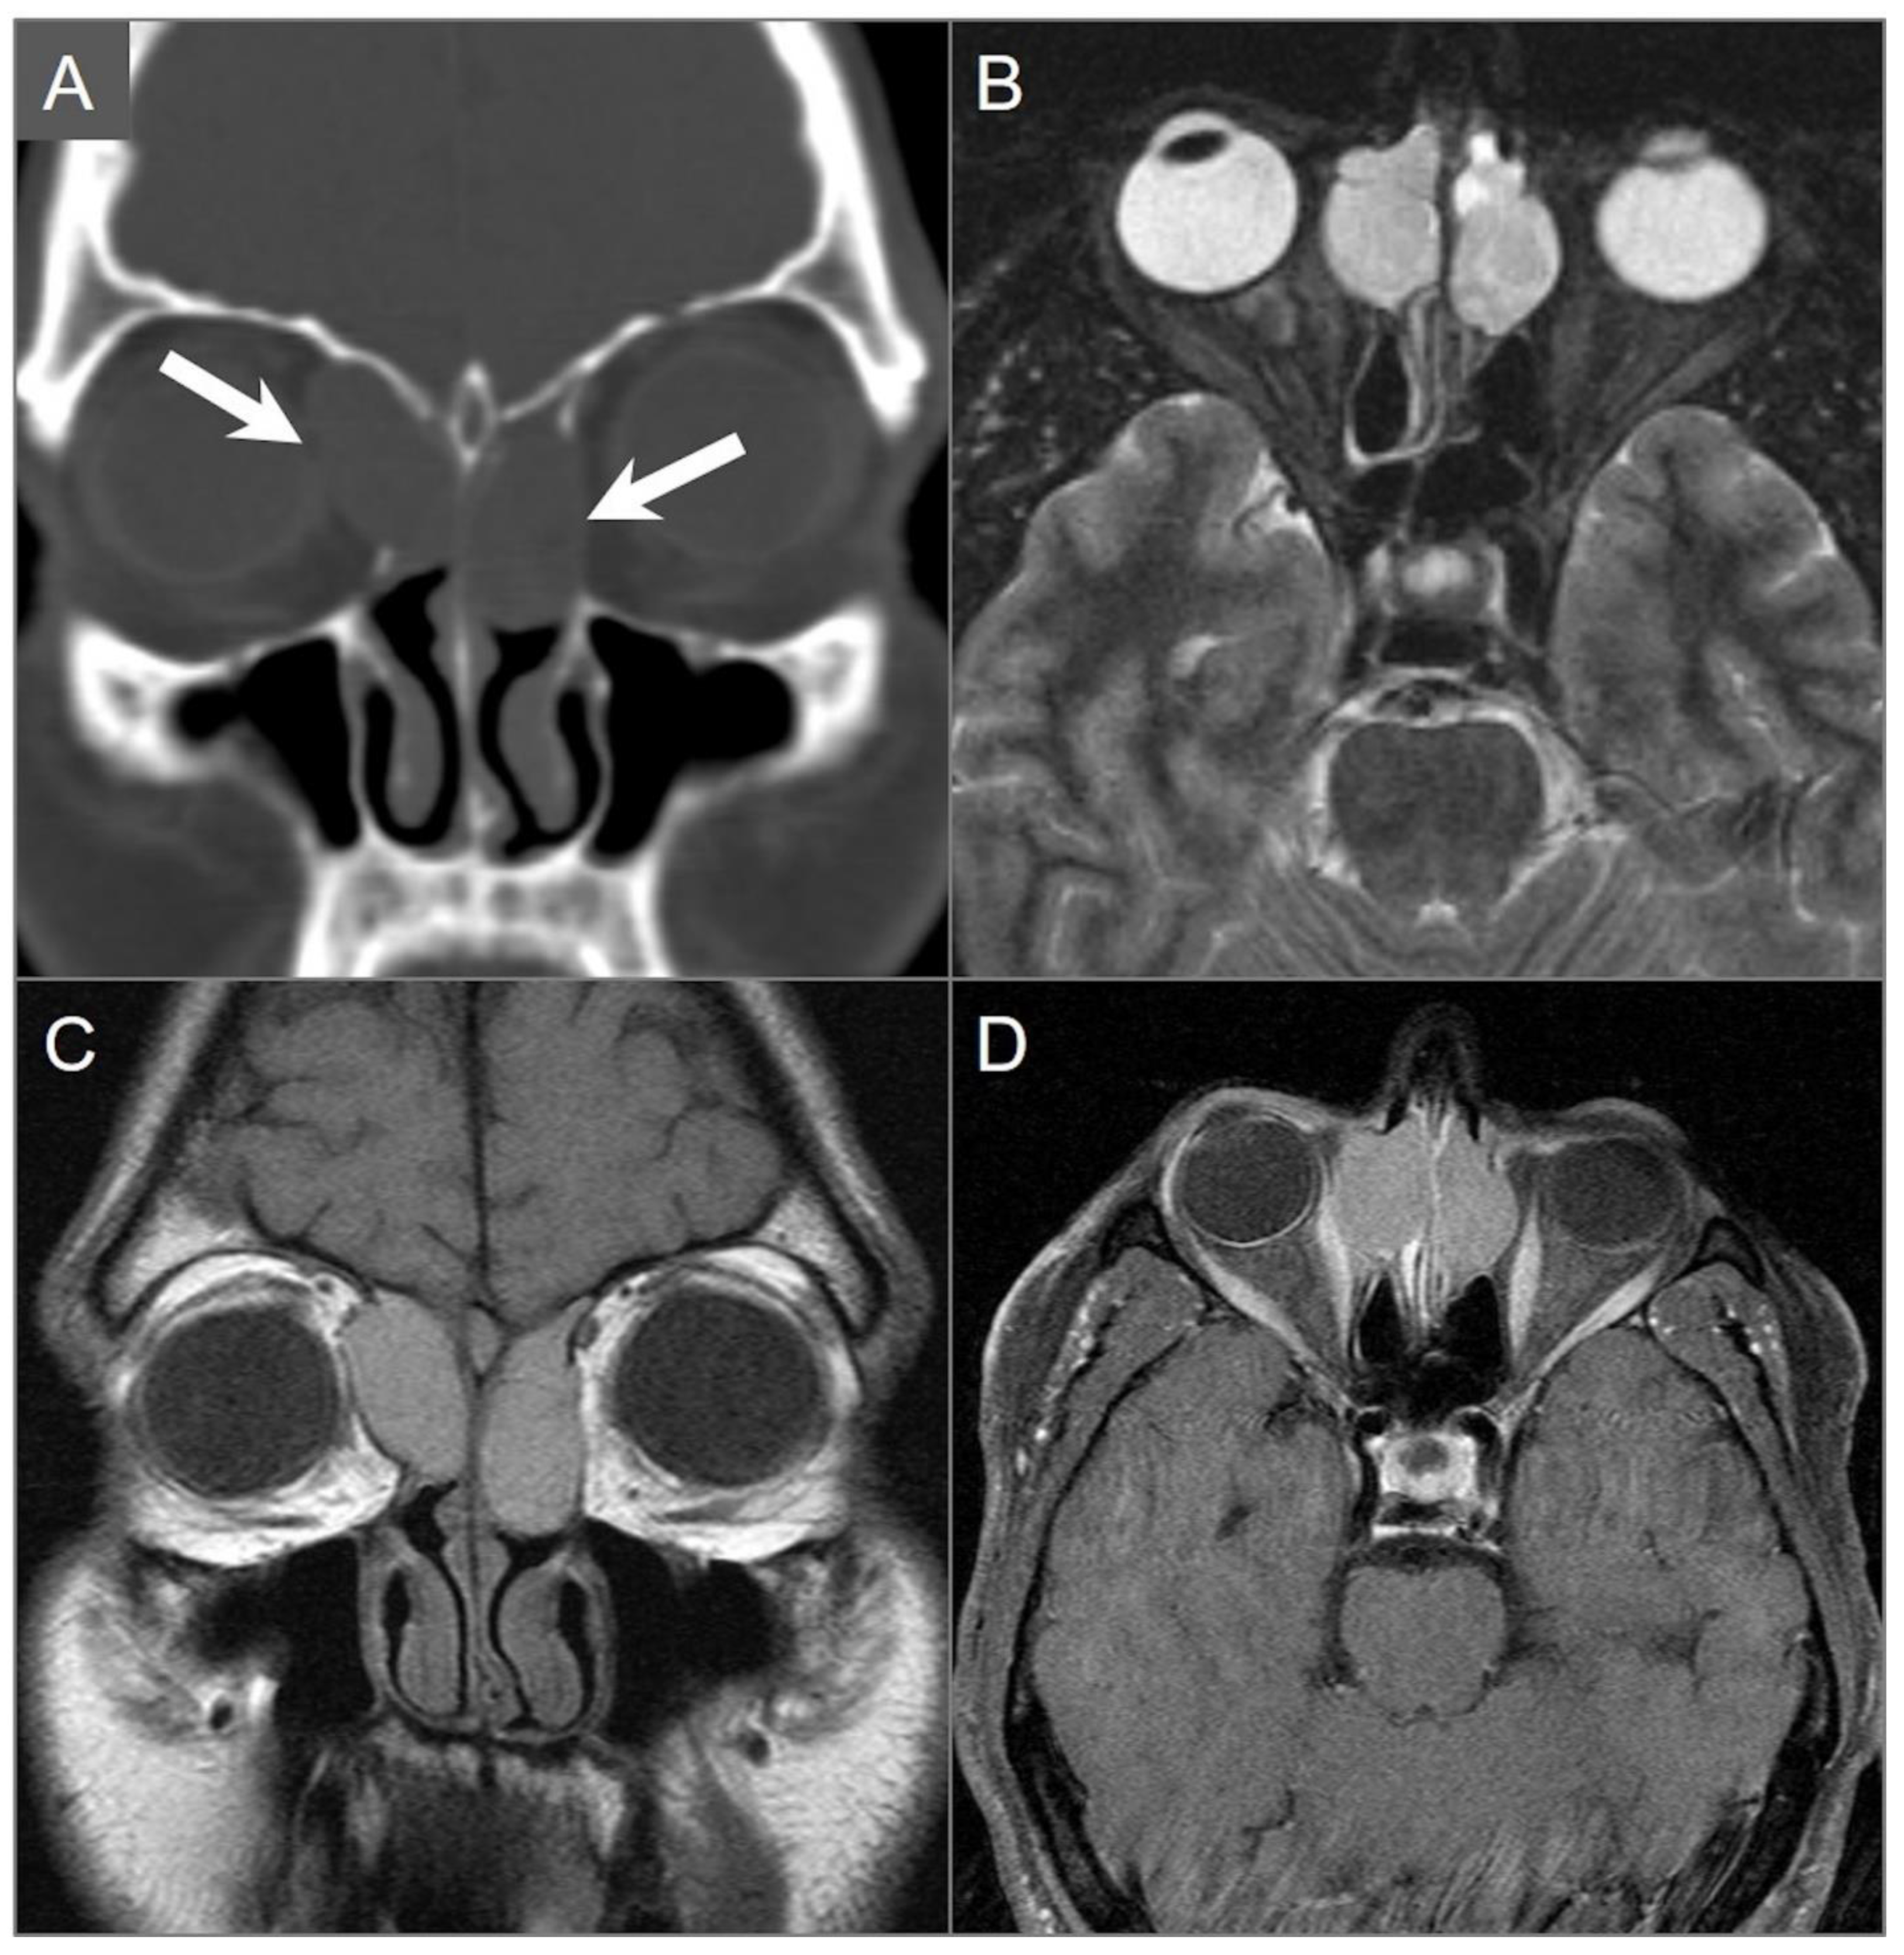

5.6. Invasive Fungal Sinusitis